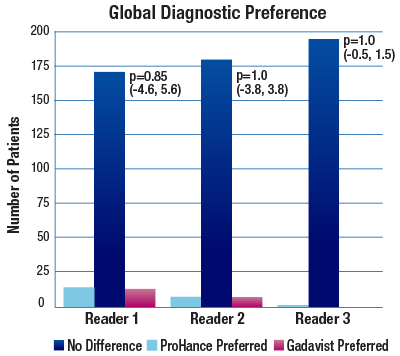

The 95% confidence intervals for all qualitative assessments confirm that ProHance is not inferior to Gadavist.1

No significant differences noted by any reader for any parameter:1

- Global Diagnostic Preference